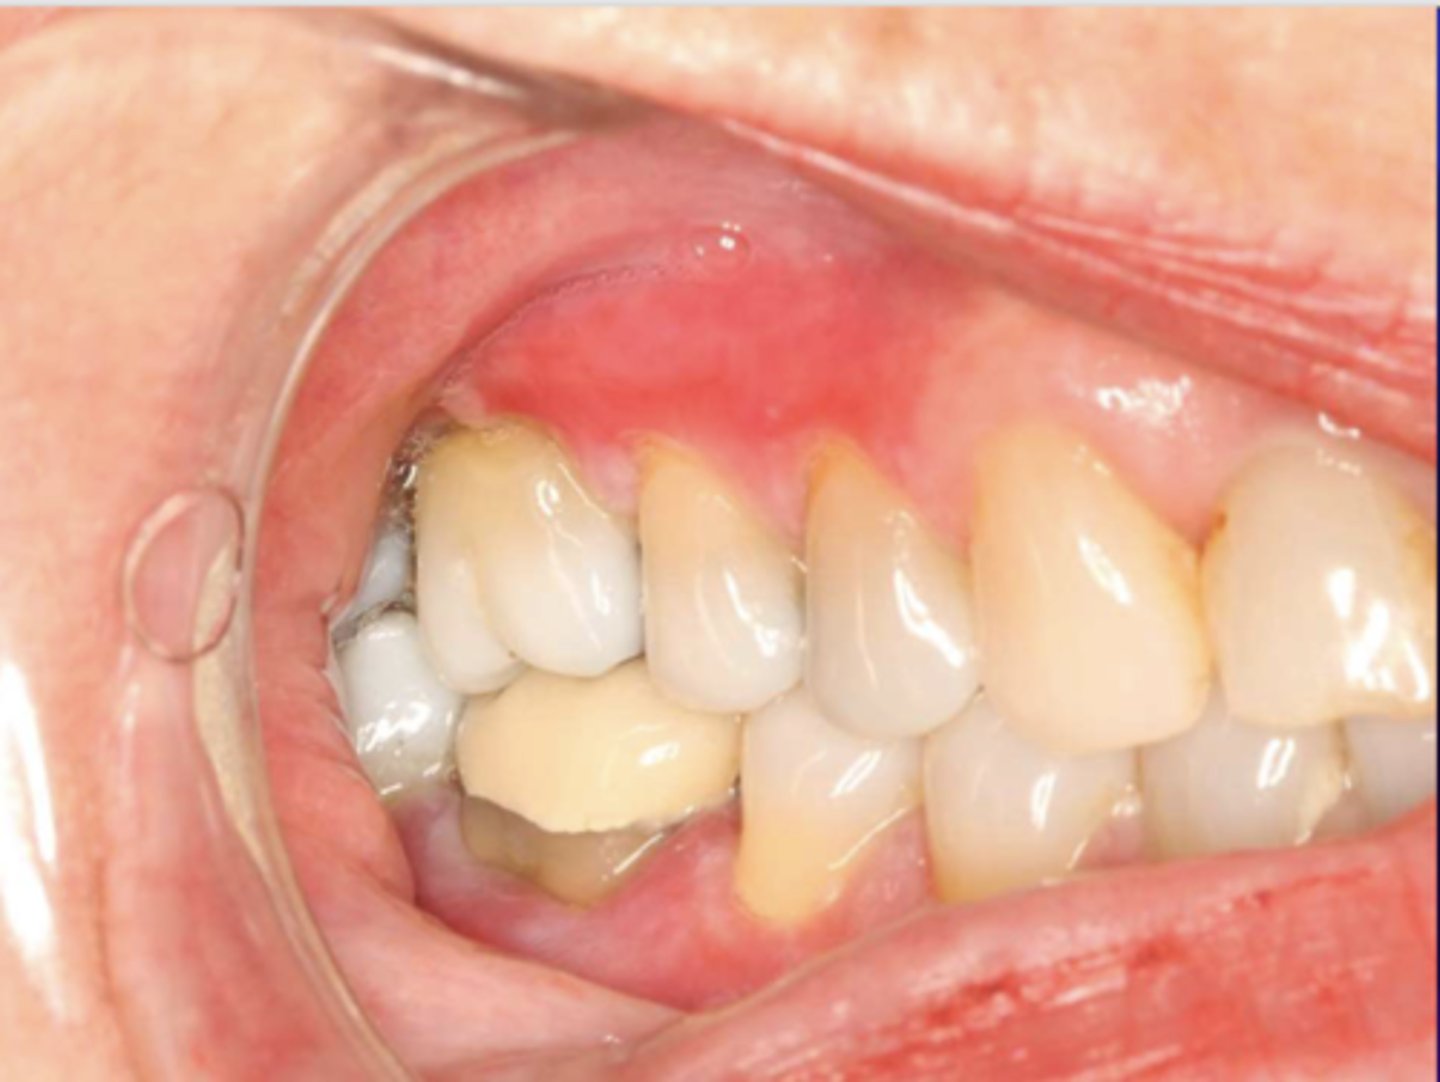

This is the clinical manifestation of which condition?

What condition?

desquamative gingivitis